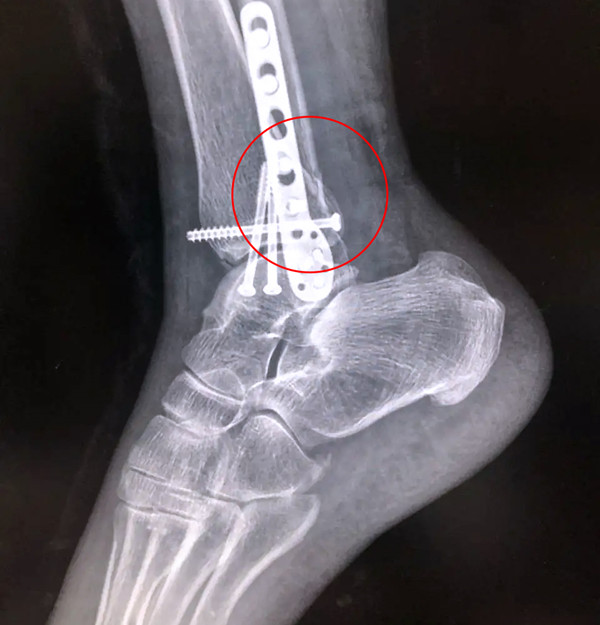

【医疗科普】Pilon骨折

有一种特殊类型的踝关节骨折,可能在X影像平片上就不能显示出来,它就是胫骨的关节面往里塌陷,我们又称之为叫“Pilon骨折”。当它往里塌陷后,我们在X影像平片上可能看不出来它是否塌陷,但是我们在CT上可以360°看到踝关节的影像,这样就可以看出患者是否存在踝关节塌陷的骨折。同样道理,我们在做Pilon骨折手术的时候,普通二维的X影像并不能判断我们手术复位情况的好坏,这个时候如果医生手上有能够照三维影像的工具,那么对于医生的准确手术是非常有好处的。